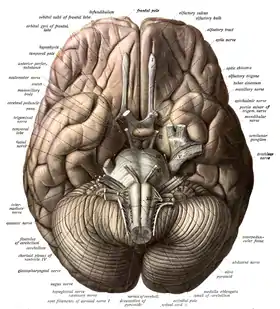

The brainstem, resembling a stalk, attaches to and leaves the cerebrum at the start of the midbrain area. The brainstem includes the midbrain, the pons, and the medulla oblongata. Behind the brainstem is the cerebellum (Latin: little brain).[7]

Cerebellum

The cerebellum is divided into an anterior lobe, a posterior lobe, and the flocculonodular lobe.[31] The anterior and posterior lobes are connected in the middle by the vermis.[32] Compared to the cerebral cortex, the cerebellum has a much thinner outer cortex that is narrowly furrowed into numerous curved transverse fissures.[32] Viewed from underneath between the two lobes is the third lobe the flocculonodular lobe.[33] The cerebellum rests at the back of the cranial cavity, lying beneath the occipital lobes, and is separated from these by the cerebellar tentorium, a sheet of fibre.[34]

It is connected to the brainstem by three pairs of nerve tracts called cerebellar peduncles. The superior pair connects to the midbrain; the middle pair connects to the medulla, and the inferior pair connects to the pons.[32] The cerebellum consists of an inner medulla of white matter and an outer cortex of richly folded grey matter.[34] The cerebellum's anterior and posterior lobes appear to play a role in the coordination and smoothing of complex motor movements, and the flocculonodular lobe in the maintenance of balance[35] although debate exists as to its cognitive, behavioural and motor functions.[36]

Brainstem

The brainstem lies beneath the cerebrum and consists of the midbrain, pons and medulla. It lies in the back part of the skull, resting on the part of the base known as the clivus, and ends at the foramen magnum, a large opening in the occipital bone. The brainstem continues below this as the spinal cord,[37] protected by the vertebral column.

Ten of the twelve pairs of cranial nerves[lower-alpha 1] emerge directly from the brainstem.[37] The brainstem also contains many cranial nerve nuclei and nuclei of peripheral nerves, as well as nuclei involved in the regulation of many essential processes including breathing, control of eye movements and balance.[38][37] The reticular formation, a network of nuclei of ill-defined formation, is present within and along the length of the brainstem.[37] Many nerve tracts, which transmit information to and from the cerebral cortex to the rest of the body, pass through the brainstem.[37]